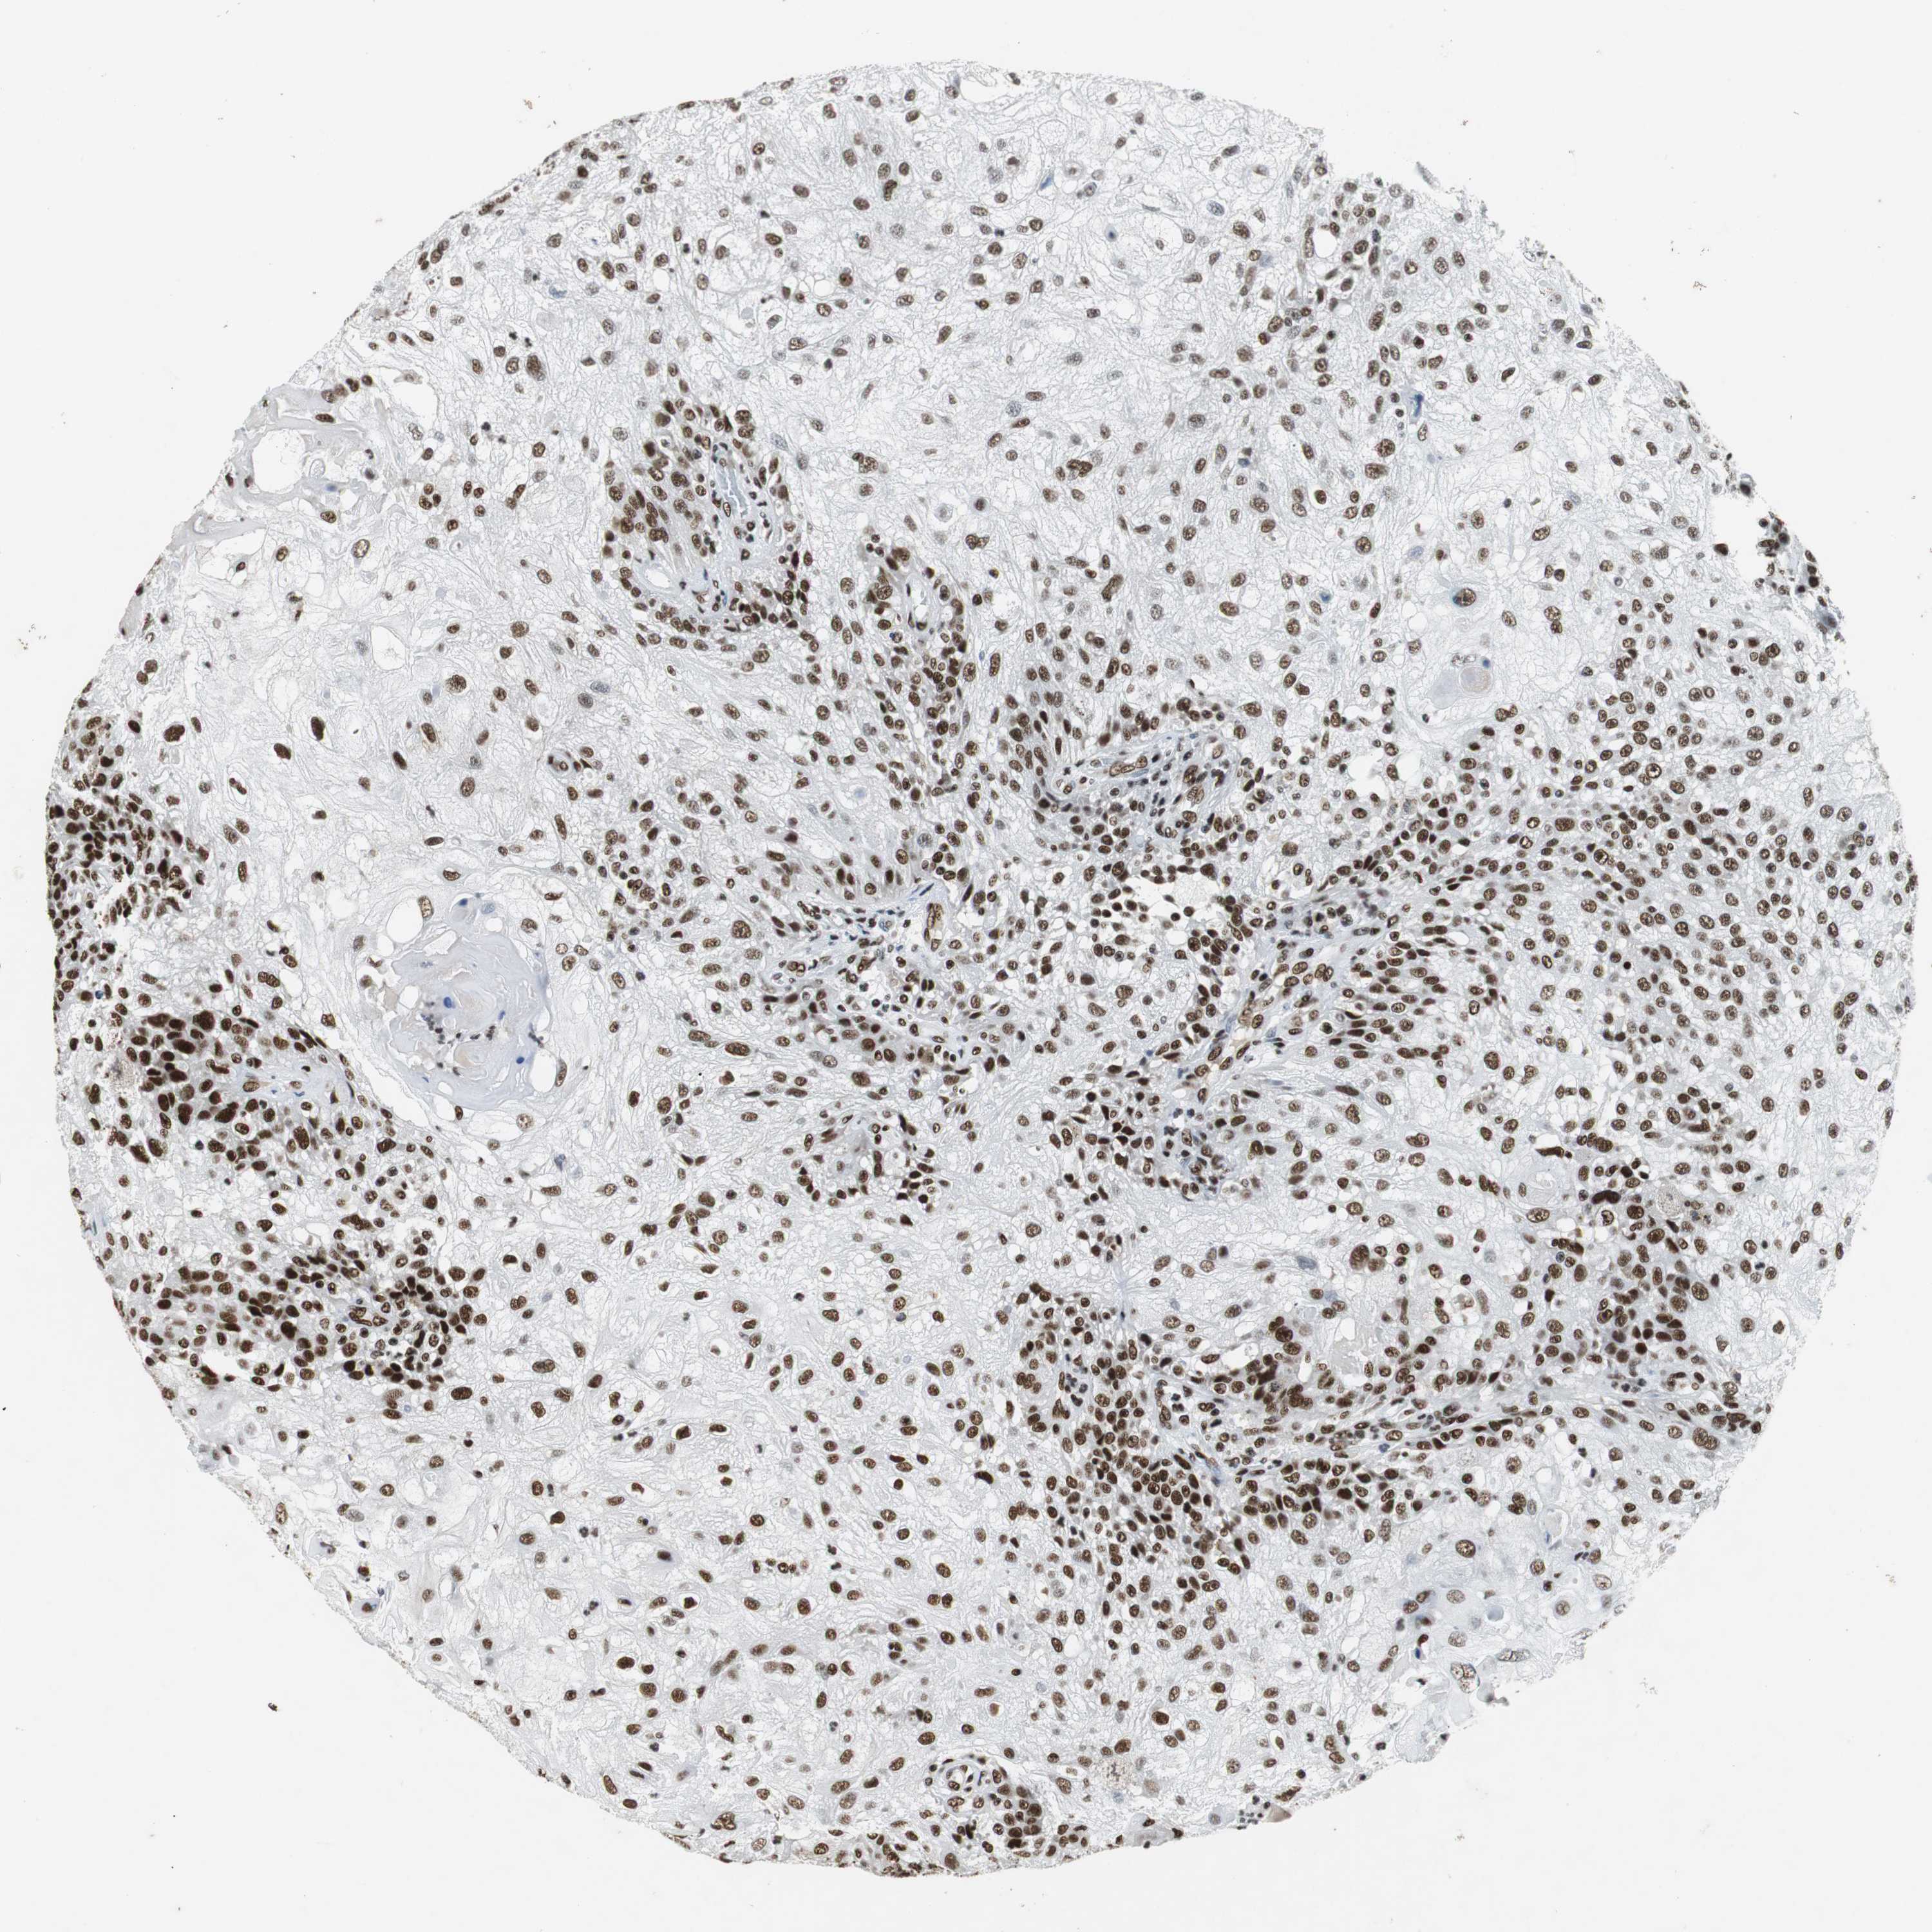

SKIN CANCER - Protein expressioni

A mouse-over function shows sample information and annotation data. Click on an image to view it in a full screen mode. Samples can be filtered based on level of antibody staining by selecting one or several of the following categories: high, medium, low and not detected. The assay and annotation is described here.

Antibody stainingi

Antibody staining in the annotated cell types in the current human tissue is reported as not detected, low, medium, or high, based on conventional immunohistochemistry profiling in selected tissues. This score is based on the combination of the staining intensity and fraction of stained cells.

Each image is clickable and will lead to virtual microscopy that enables deeper exploration of all samples and also displays staining intensity scores, fraction scores and subcellular localization as well as patient and tissue information for each sample.

Antibody HPA035174

Antibody CAB005167

Staining

Medium

Moderate

>75%

Location

Squamous cell carcinoma, NOS

Squamous cell carcinoma, metastatic, NOS